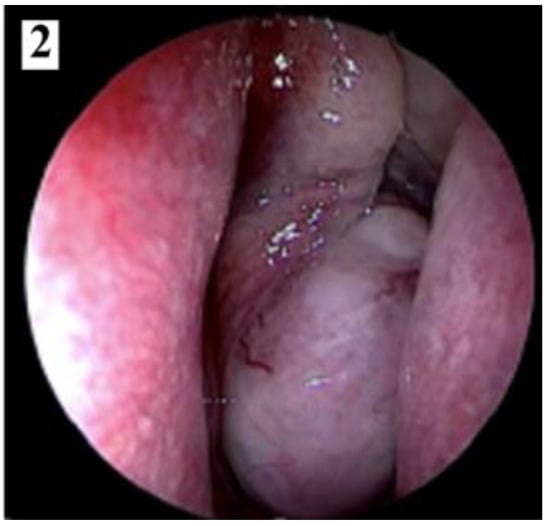

Figure 2.

Smooth, lobulated, pale or grey-red, intensely congestive, compressible mass (part 2).